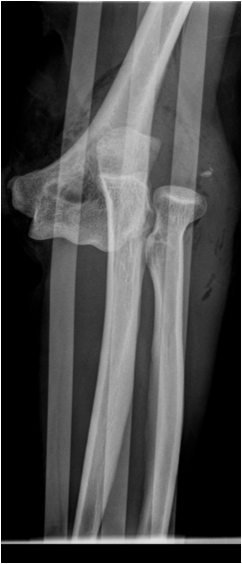

Fig. 12. A) Complete dislocation with contraction in the elbow joint. Ulna and radius are both dislocated and dorsally displaced. B.) Anterior and inferior dislocation of the humerus.